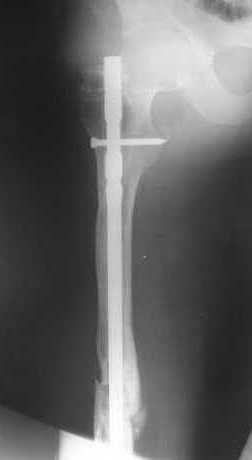

27 марта выполнено удаление блокирующих винтов (сломанный винт пришлось высверливать цапфен-бором), сломанного штифта (дистальный фрагмент удален через канал, образованный разверткой из коленного сустава - image 4),

рассверливание костно-мозгового канала, реостеосинтез штифтом UFN (при проведении штифта в дистальном отломке мы использовали поляризующий винт, диаметр штифта 10 мм). После операции в связи гемартрозом дважды (на 1 и 3 сутки) выполняли пункцию коленного сустава. Сейчас признаков скопления жидкости в полости сустава нет. Послеоперационные рентгенограммы - images 5, 6, 7.